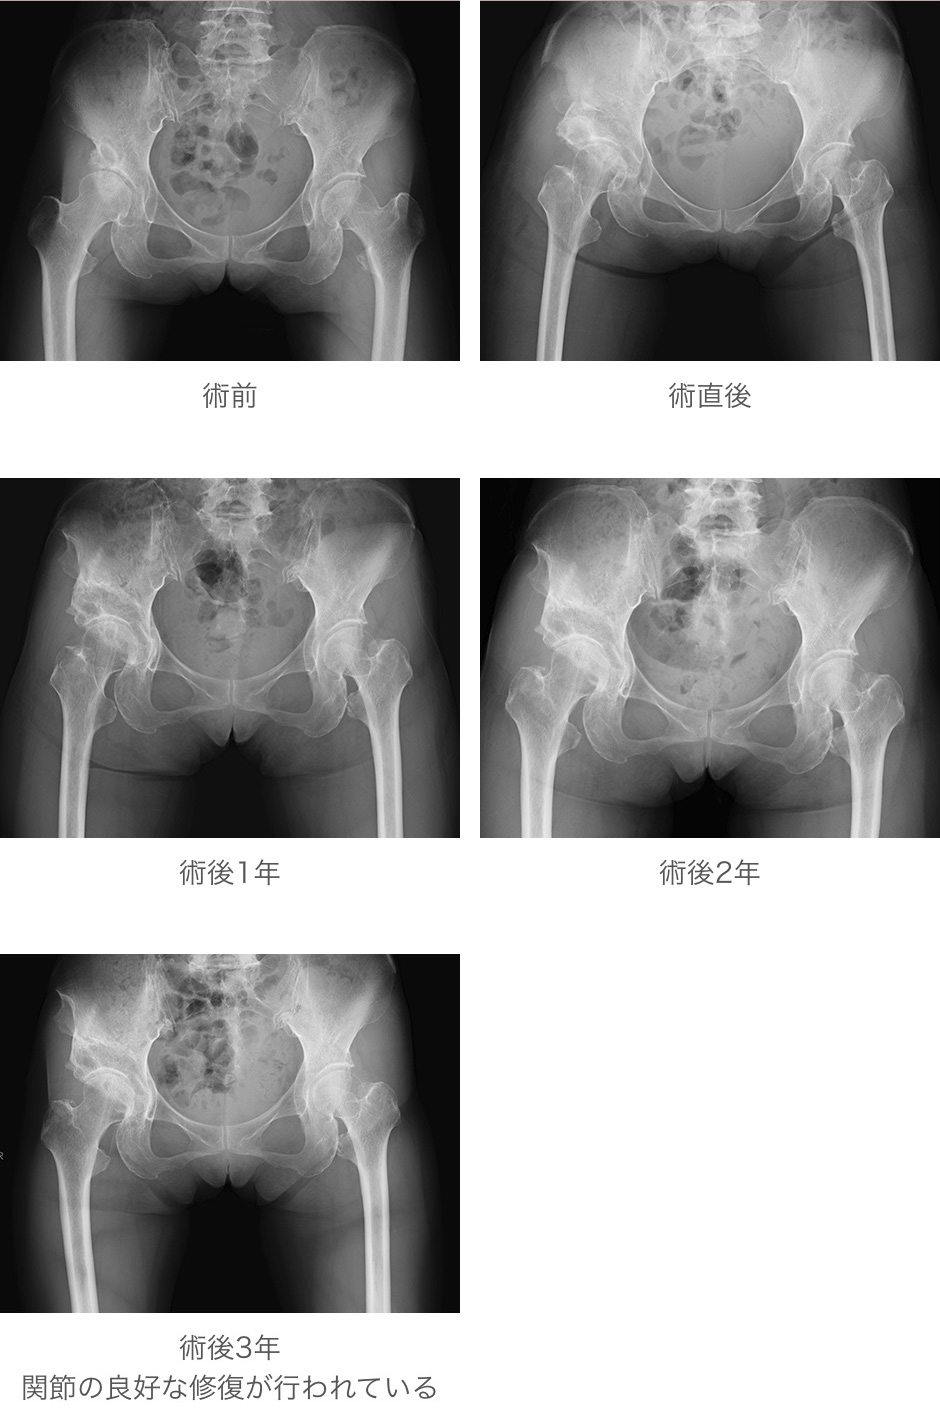

• 症例3:大腿骨頭回転骨切り術(外傷性大腿骨頭壊死に対して) 大腿骨頭回転骨切り術(外傷性大腿骨頭壊死に対して) 大腿骨頭回転骨切り術(外傷性大腿骨頭壊死に対して)

一般的にはレントゲン上変形が軽度な前・初期関節症には寛骨臼回転骨切り術や大腿骨転子間弯曲内反骨切り術、レントゲン上変形が高度な進行期、末期股関節症に対しては大腿骨外反骨切り術やキアリー骨盤骨切り術、人工股関節置換術が選択されています。当センターでは、適応のある方には積極的に関節温存手術を実施しています。以下に代表的な症例を供覧いたします。